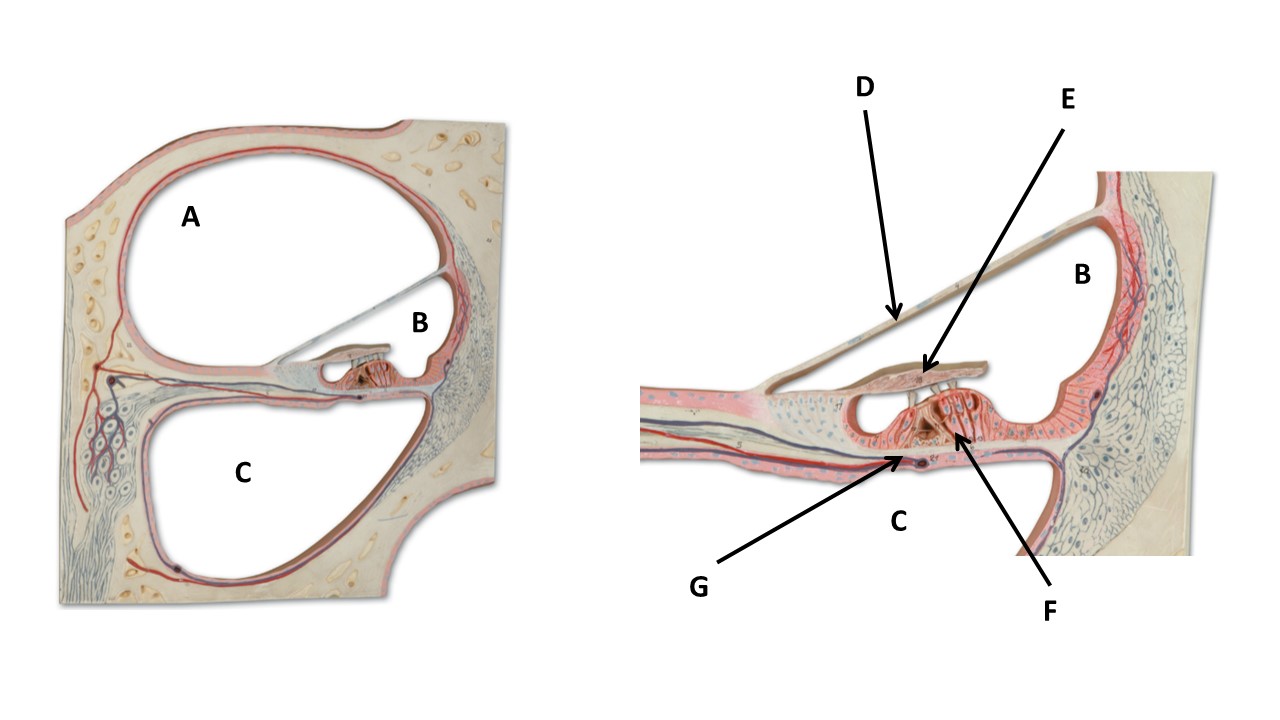

The chamber labeled B is filled with _____.

endolymph

Name the structure at the tip of arrow F.

spinal organ